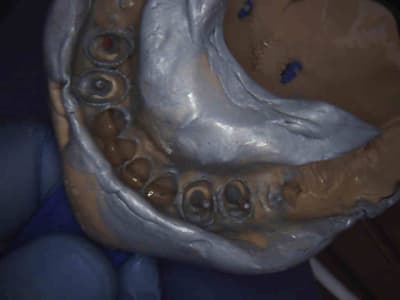

Les 4 en une heure et quart pulpec, taille, empreinte, provisoires. Tarif CMU, rentable ! -)))))

Je ne suis pas mesquin ! Pour les détails, ce sera réglé au bloc, c'est pas que les dents seront difficiles à enlever, c'est plutot les bombes à retardement sous jacentes le probleme ! -)))))

1 xw6yrt - Eugenol

Images jm2g2g - Eugenol

oh pinaise.. c'est pire que le l’Irak ton bazar !!